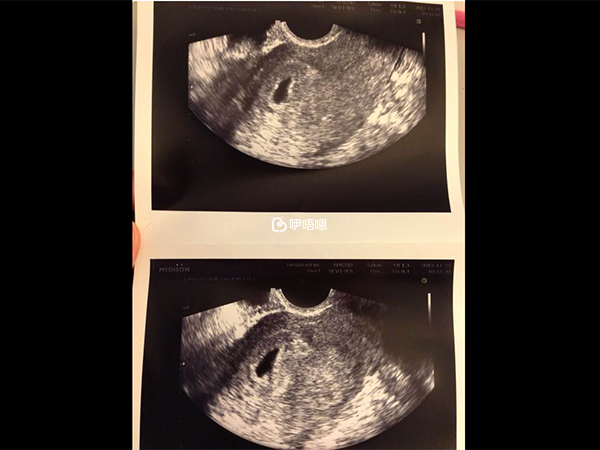

二月自然週期,移植一枚5AA囊胚,14天后驗尿試紙秒顯雙槓。整整6年求子之路,頓時淚湧。35天做陰超確認宮內好孕卵黃囊可見!

50天已見胎芽胎心,當大夫把寶寶的心跳聲放大聲給我們聽的時候,緊緊握著老公的手,我躺在椅子上再次忍不住淚崩……